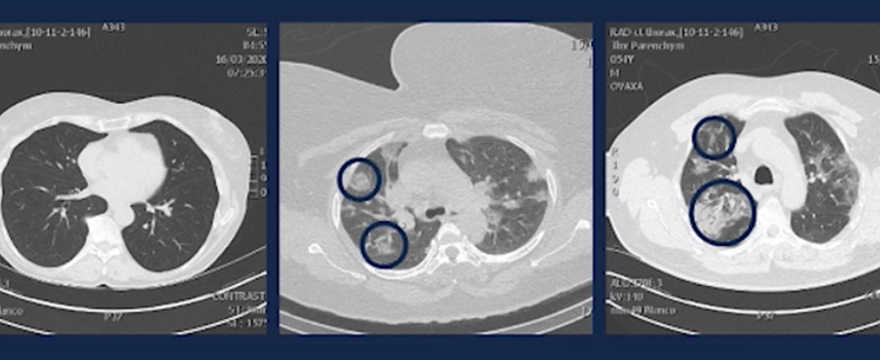

Ignace Demeyer pokazał prześwietlenia płuc trzech różnych pacjentów z koronawirusem:

- na pierwszym zdjęciu widać zdrowe płuca,

- natomiast na drugim widać płyn, który wypełnia od 20 do 25 procent objętości pęcherzyków płucnych,

- trzecie zdjęcie przedstawia płuca, w których płyn zajmuje już 80-90 proc.,

- następny skan, to pacjent z zagrożeniem życia.